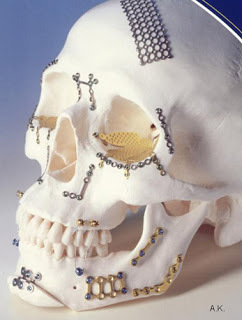

Here's the longer answer. In a situation where someone had enough trauma to the skull to warrant surgery, it's possible that they would need titanium implants during the surgery. In one scenario, only titanium screws and thin, narrow plates would be used to put broken pieces of skull together. In a situation where the skull injury is too large to be covered by native skull pieces, a larger piece of plating or mesh might be used.

Photo CreditI sort of have a fondness for titanium, so here are some more thoughts.

Photo CreditI sort of have a fondness for titanium, so here are some more thoughts.

Why is titanium used in medical implants? Titanium is an inert metal that is biocompatible with the human body, so rejection isn't an issue. It's also able to osseointegrate, meaning that bone can grow right up to that metal, without having scar tissue in between.

Do they have to stay there forever? For the above scenario, yes. For things like artificial joints, those tend to have a more limited life span of 15-20 years (or more) due to the wear and tear of the components of the actual socket. Other life span factors include the health of the patient, bone health, and activity levels.

Will the patient stick to an MRI machine, or a giant junk yard magnet?

No. Titanium is non-ferromagnetic, so MRIs are safe (however, if it's near the area being examined, the implant can cause blurring or streaks, called "artifact," of the images.)

How about metal detectors? Depending on the detector or screening tool at the airport/school/building, titanium implants could set off an alarm.

Other bodily uses? Titanium dioxide, which is the most common form of titanium found naturally, is also the white stuff used in physical sunblocks. Lots of body piercing jewelry is also made with implant grade titanium.

Here's the longer answer. In a situation where someone had enough trauma to the skull to warrant surgery, it's possible that they would need titanium implants during the surgery. In one scenario, only titanium screws and thin, narrow plates would be used to put broken pieces of skull together. In a situation where the skull injury is too large to be covered by native skull pieces, a larger piece of plating or mesh might be used.

Photo CreditI sort of have a fondness for titanium, so here are some more thoughts.

Photo CreditI sort of have a fondness for titanium, so here are some more thoughts.Why is titanium used in medical implants? Titanium is an inert metal that is biocompatible with the human body, so rejection isn't an issue. It's also able to osseointegrate, meaning that bone can grow right up to that metal, without having scar tissue in between.

Do they have to stay there forever? For the above scenario, yes. For things like artificial joints, those tend to have a more limited life span of 15-20 years (or more) due to the wear and tear of the components of the actual socket. Other life span factors include the health of the patient, bone health, and activity levels.

Will the patient stick to an MRI machine, or a giant junk yard magnet?

No. Titanium is non-ferromagnetic, so MRIs are safe (however, if it's near the area being examined, the implant can cause blurring or streaks, called "artifact," of the images.)

How about metal detectors? Depending on the detector or screening tool at the airport/school/building, titanium implants could set off an alarm.

Other bodily uses? Titanium dioxide, which is the most common form of titanium found naturally, is also the white stuff used in physical sunblocks. Lots of body piercing jewelry is also made with implant grade titanium.